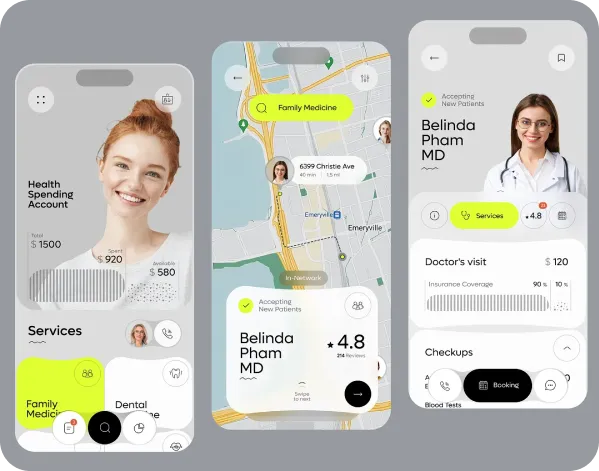

Discover Next-Gen Healthcare Management – Watch Live

Smarter Healthcare Solutions for Modern Patients

Simplifying Doctor Appointments and Healthcare Access

Virtual Healthcare Consultations Anytime, Anywhere

Intelligent Digital Assistant for Healthcare Needs